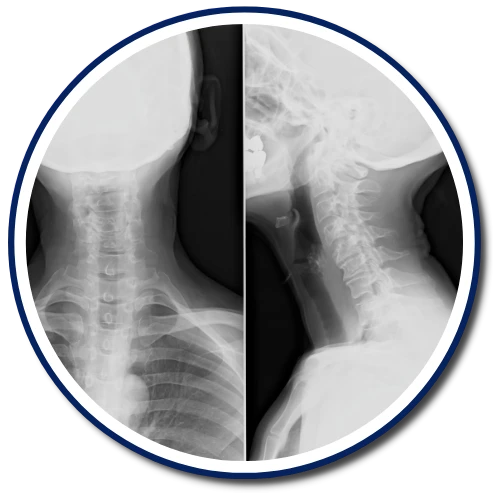

We use the Insight Subluxation Station, the only technology of its kind certified by the NASA Space Foundation. Combined with advanced digital X-ray, we objectively evaluate and monitor your neuro-spinal function to accurately locate, assess, and track subluxations.